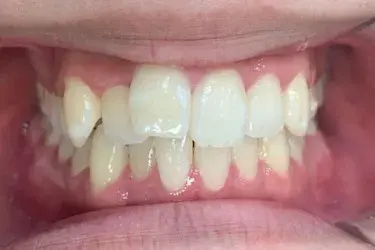

治療期間 約8カ月

治療費 23.1万円(税込)